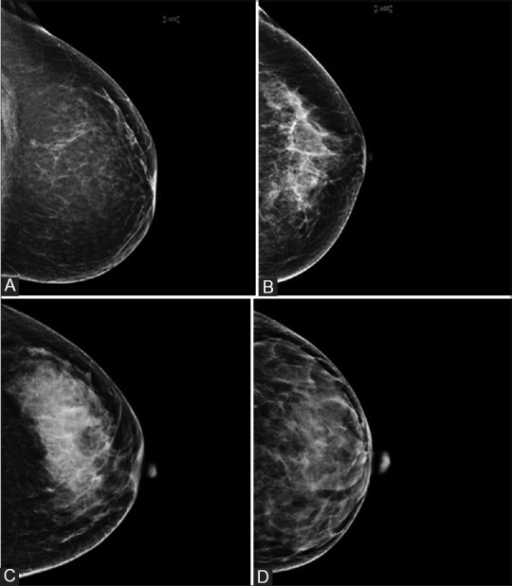

Evaluation of breast parenchymal density with QUANTRA software by S. Pahwa, S. Hari, S. Thulkar, S. Angraal is licensed under CC BY-NC-SA 3.0

Breast density is graded from 1-4, indicating the amount of fibroglandular tissue in the breast.

One: This indicates the breast is composed almost entirely of fat, and fibroglandular tissue makes up less than 25% of the breast. Around one in 10 women will have this result.

Two: Fibroglandular tissue makes up 25-50% of the breast. Four in 10 women will have this result.

Three: This grade is given to moderately dense breasts, where fibroglandular tissue makes up 51-75% of the breast. Four in 10 women will have this result.

Four: At this grade, the breast tissue is considered extremely dense, with the breast composed of 75% fibroglandular tissue. Around one in 10 women will have this result.